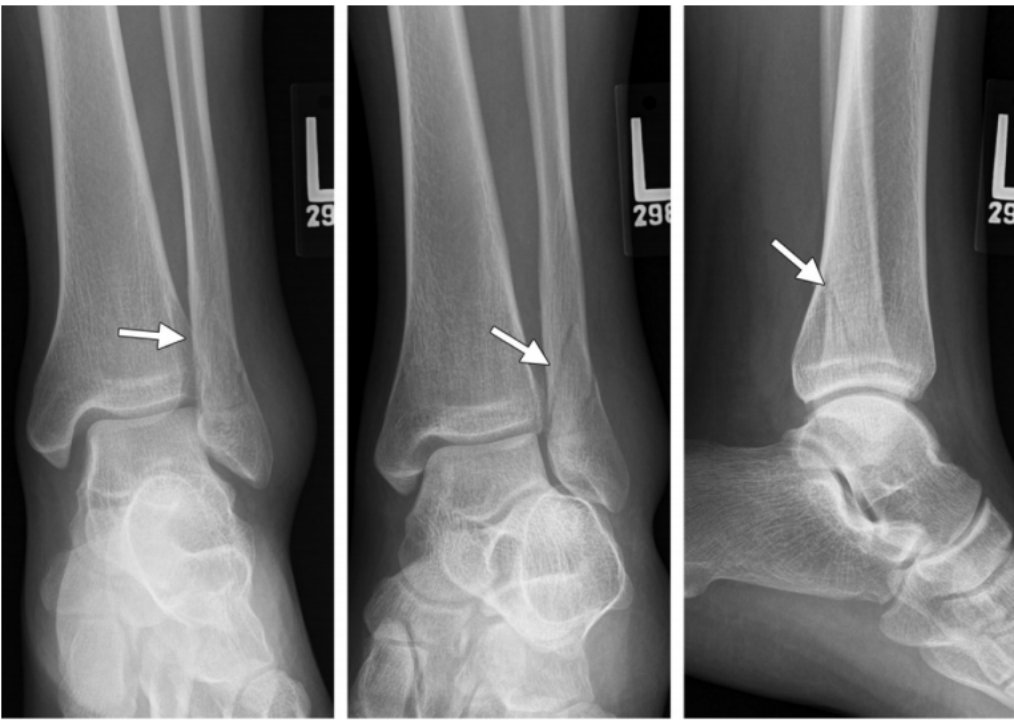

Ⅱ 度:由于距骨给腓骨施加了旋转力,导致腓骨在胫骨关节面顶部发生斜行或螺旋形骨折,骨折线一般自前下方斜向后上方。

II 度损伤 X 线片显示:胫腓骨间隙变宽,提示下胫腓前韧带断裂;腓骨螺旋形骨折;侧位片显示腓骨骨折位于下胫腓联合水平,骨折线由前下到后上,后踝无骨折。

Ⅲ 度:若外旋的力量进一步作用,可导致下胫腓后韧带断裂,或韧带在腓骨后结节附着点撕脱,或其胫骨附着点撕脱骨折(Volkmann 骨折)。

IV 度损伤 X 线片显示:胫骨腓骨间隙变宽,提示下胫腓韧带联合断裂;腓骨螺旋形骨折,腓骨骨折位于下胫腓联合水平,骨折线由前下到后上,内踝间隙增宽,提示三角韧带断裂;侧位片显示后踝无明显骨折,但下胫腓后韧带可能断裂。